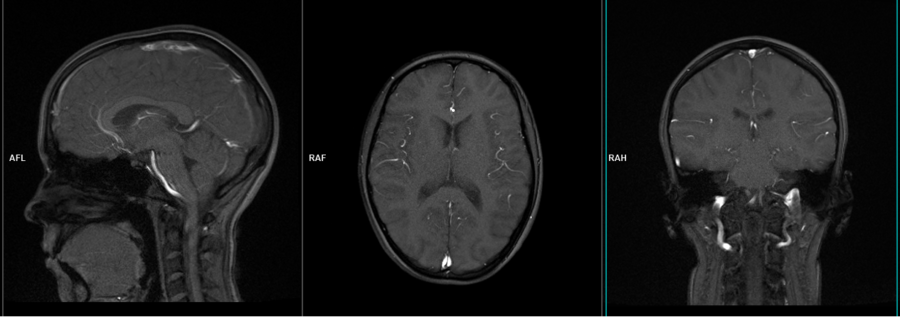

T2 FLAIR axial

Plan the axial slices on the sagittal plane and position the block parallel to the genu and splenium of the corpus callosum. Verify the planning block in the other two planes and ensure that an appropriate angle is maintained in the coronal plane, making it perpendicular to the line of the midline of the brain and the 4th ventricle. Ensure that the number of slices is sufficient to cover the entire brain from the vertex to the line of the foramen magnum.

Protocol Parameters of FLAIR

TR 7000-9000 | TE 110 | FLIP 130 | NEX 2 | SLICE 3MM | MATRIX 320X320 | FOV 210-230 | PHASE R>L | GAP 10% | TI 2500 |